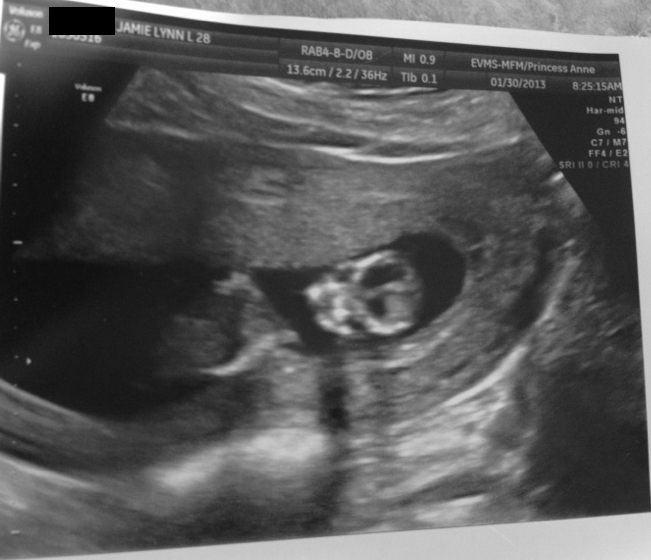

Adventures in Baby Making 16 Weeks Ultrasound Pics

from adventuresinbabymakin.blogspot.com